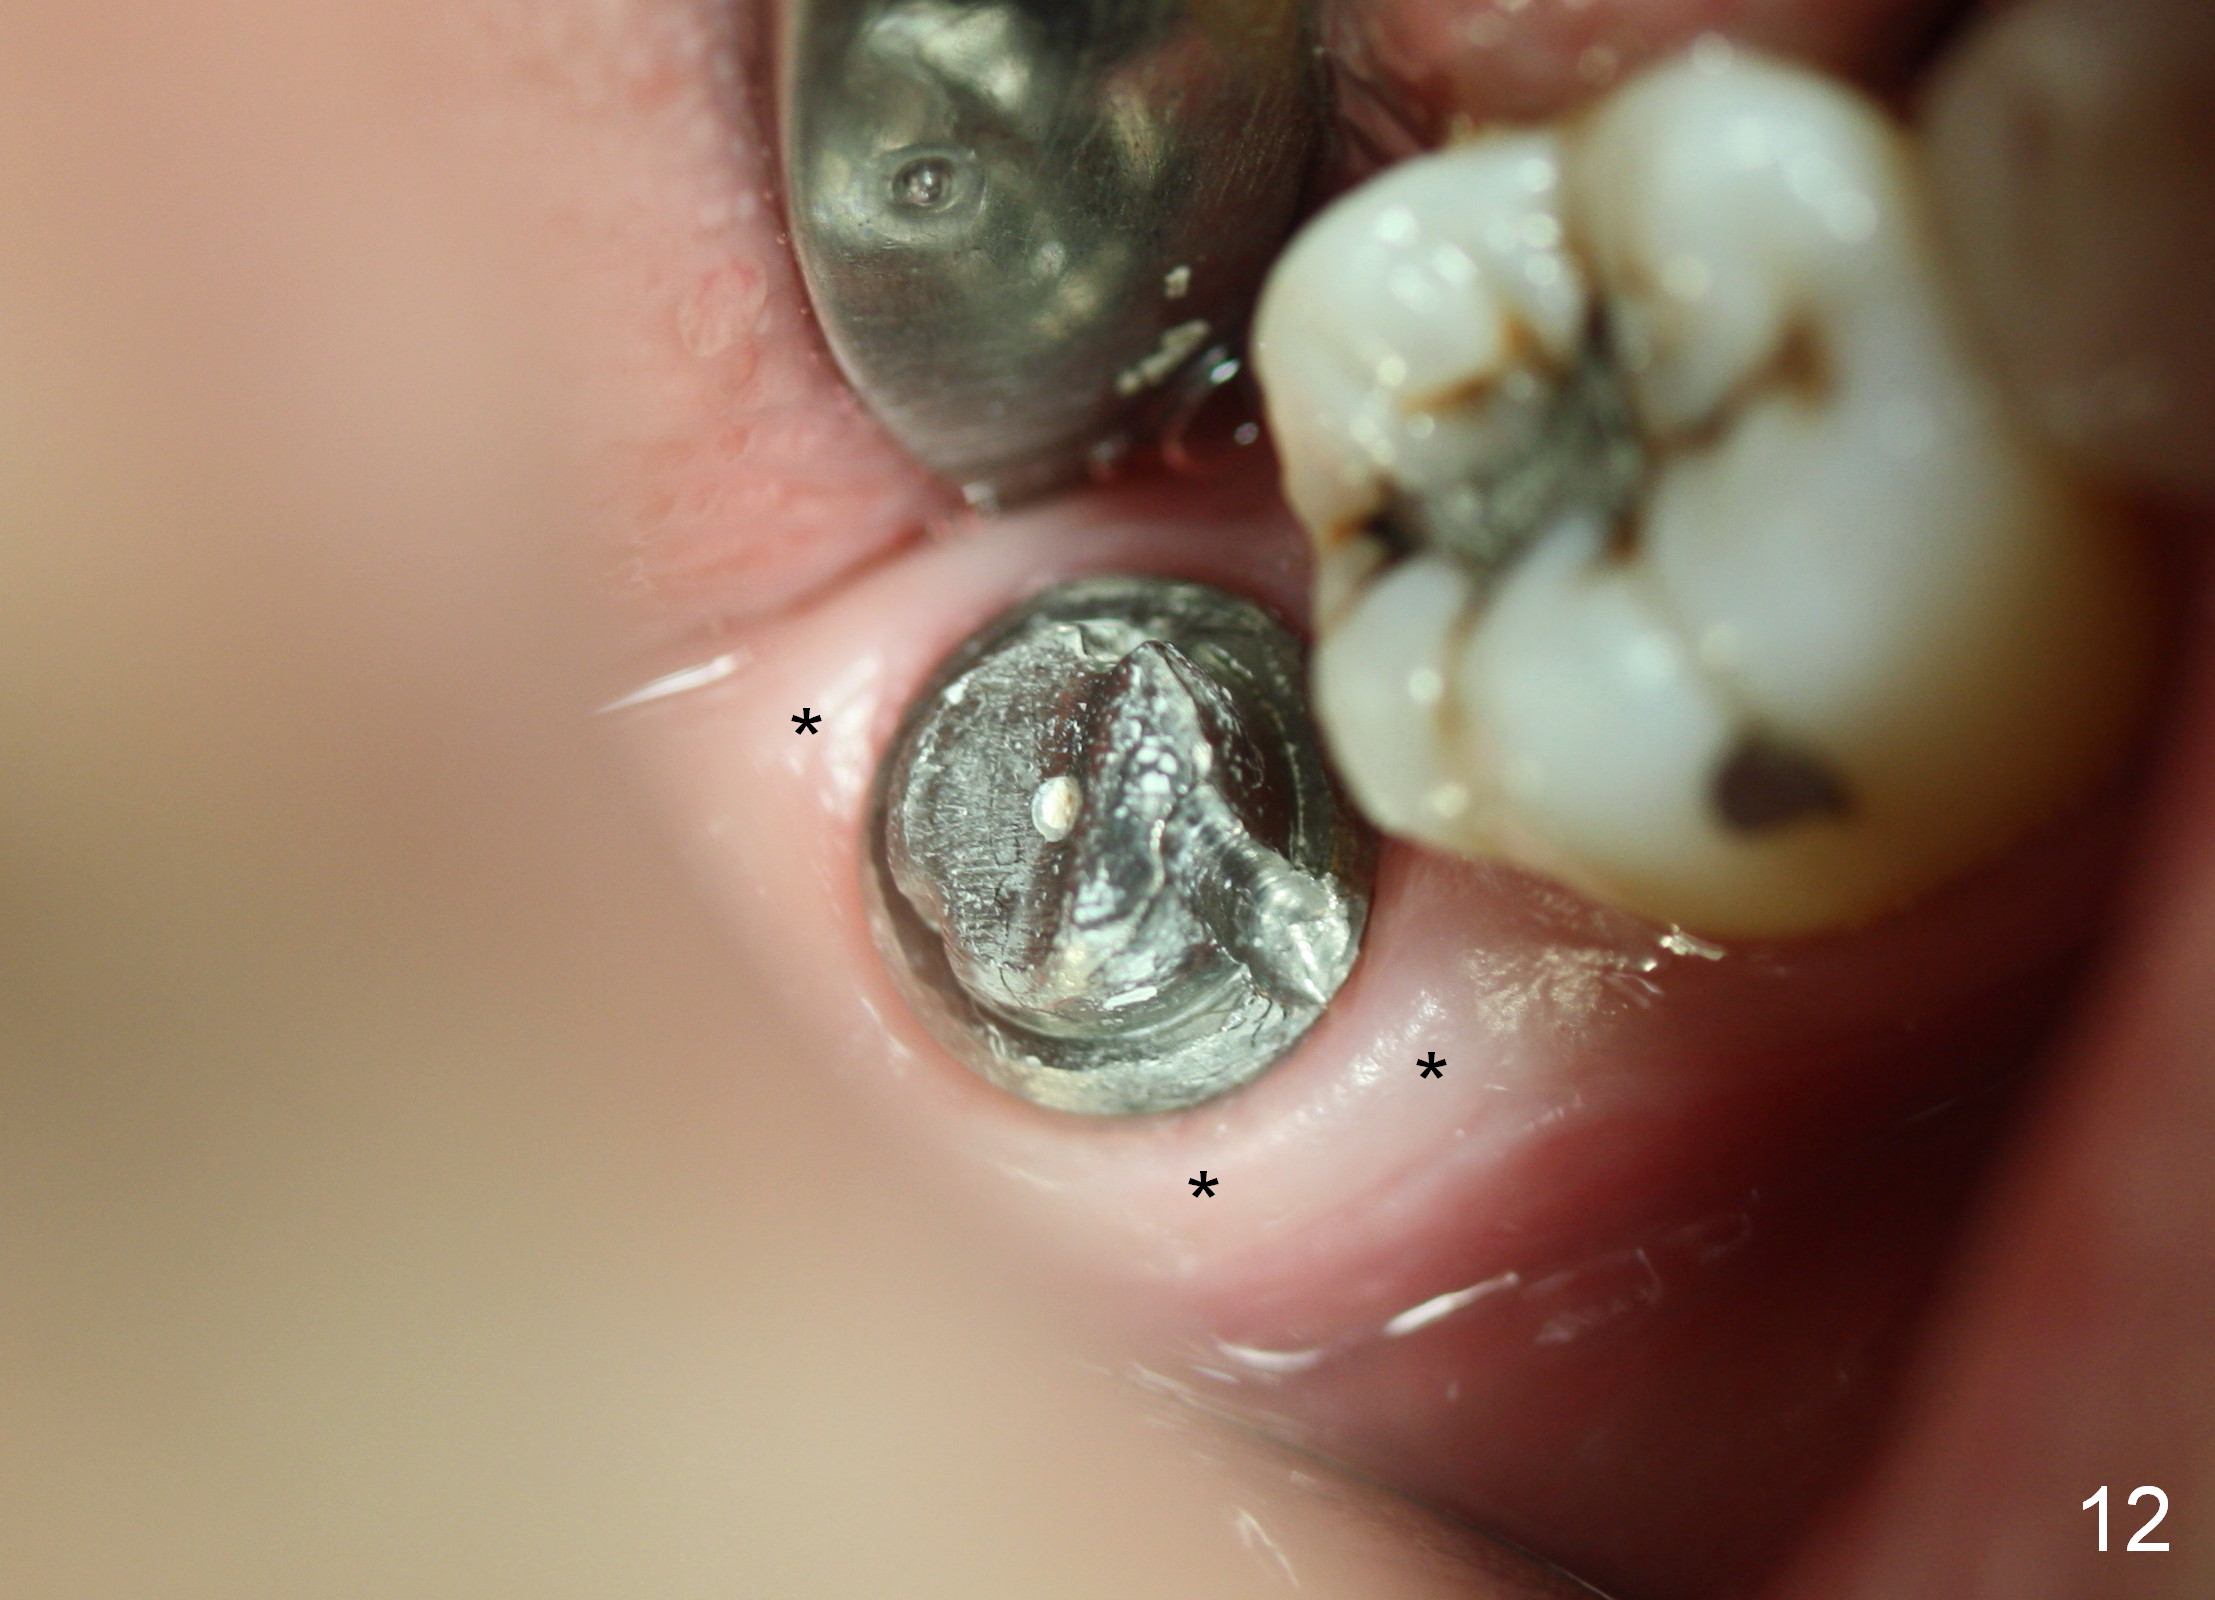

The gingiva forms a band (cuff) around the implant (Fig.11 *) and bone has apparently filled the peri-implant gap (Fig.13 *) 3.5 months postop. The gingival cuff is present immediately pre-crown cementation (Fig.12 *). The bone density around the implant continues to increase 2 and 7 months post cementation (Fig.14,15), in spite of retention of residual cement distally (<).